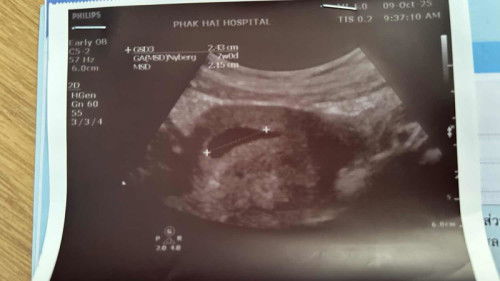

7สัปดาห์แล้วยังไม่พบตัว มีใครเป็นบ้างค่ะ

เจอกันตอนกี่วิคบ้างค่ะ กังวลมากๆ เคยเป็นท้องลม มาก่อนค่ะ #ขอบคุณสำหรับคอมเม้นล่วงหน้าค่ะ